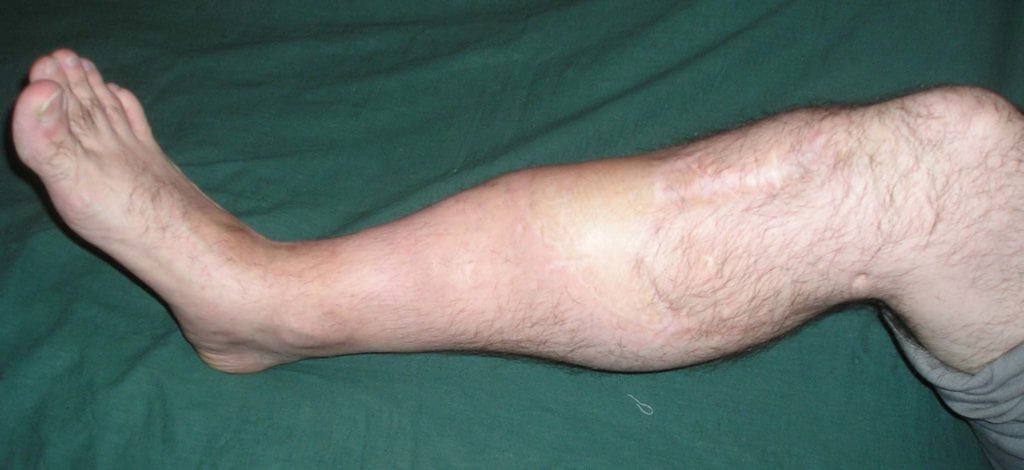

Ложный сустав – это массивный дефект кости, который возникает из-за неправильного сращения перелома. Чаще всего он формируется в области голени. Реже поражается надколенник, ключица, ладьевидная, плечевая, лучевая, локтевая или бедренная кости. По статистике, псевдоартроз выявляют у 0,5-27% людей с переломами в анамнезе. От патологии чаще страдают лица, перенесшие открытые или огнестрельные ранения.

Больные с псевдоартрозом практически всегда жалуются на открытые или закрытые переломы в анамнезе. На протяжении многих месяцев после травмы их беспокоит постоянная боль, аномальная подвижность кости и характерные щелчки при движениях. Если ложный сустав локализуется на нижней конечности, больному становится трудно ходить и вести привычный образ жизни.

Отсутствие квалифицированной медицинской помощи может иметь для человека ужасные последствия. В лучшем случае его будут беспокоить постоянные боли, а функция конечности останется нарушенной. В худшем у больного разовьется выраженная деформация ноги или руки, что приведет к инвалидности.